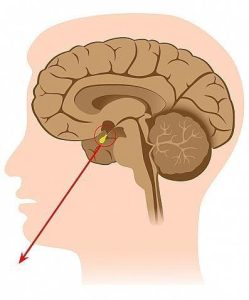

يتعرض الكثير من الأشخاص إلى الإصابة بالأورام التي تستهدف الغدة النخامية، وفي الغالب تكون هي أورام حميدة، وغير خبيثة، تستهدف تلك الغدة، التي تقع في منطقة قاعدة الدماغ، ويكون مكانها خلف الأنف مباشرة، ولا يزيد حجمها عن حجم حبة البازلاء، وتحت عنوان تجربتي مع ورم الغدة النخامية، خاض الكثيرون تجارب واتبعوا طرق لعلاج الغدة والأورام بداية من من استعمال العقاقير والأدوية، التي تستطيع التحكم في نمو الورم وتطوره، وآخرون خاضوا عملية استئصال الورم ذاته.

في البداية يجب التعريف بورم الغدة النخامية، بأنه عبارة عن خلايا تنطور بشكل وطريقة شاذة في الغدة النخامية، وتعمل عدد من أورام الغدة النخامية إلى إفراز الهرمونات بإفراط، وخاصة تلك التي تنظم مهام جسد الإنسان الضرورية، كما ينتج عن بعض أورام الغدة النخامية مستويات أضعف من هرمونات الغدة النخامية.

- من أكثر المضاعفات شيوعًا لورم الغدة النخامية هي فقدان الرؤية، حيث أن تلك الغدة تقع في مكان تقابل عصبي العينين، ومع ضغط الورم على أعصاب الرؤية، يحدث خلل في وظيفتها.